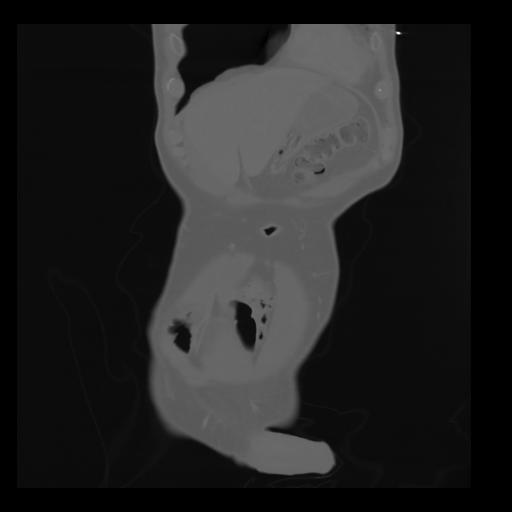

35 CUERPO,CE,Coronal,3.000,CUERPO,Coronal,